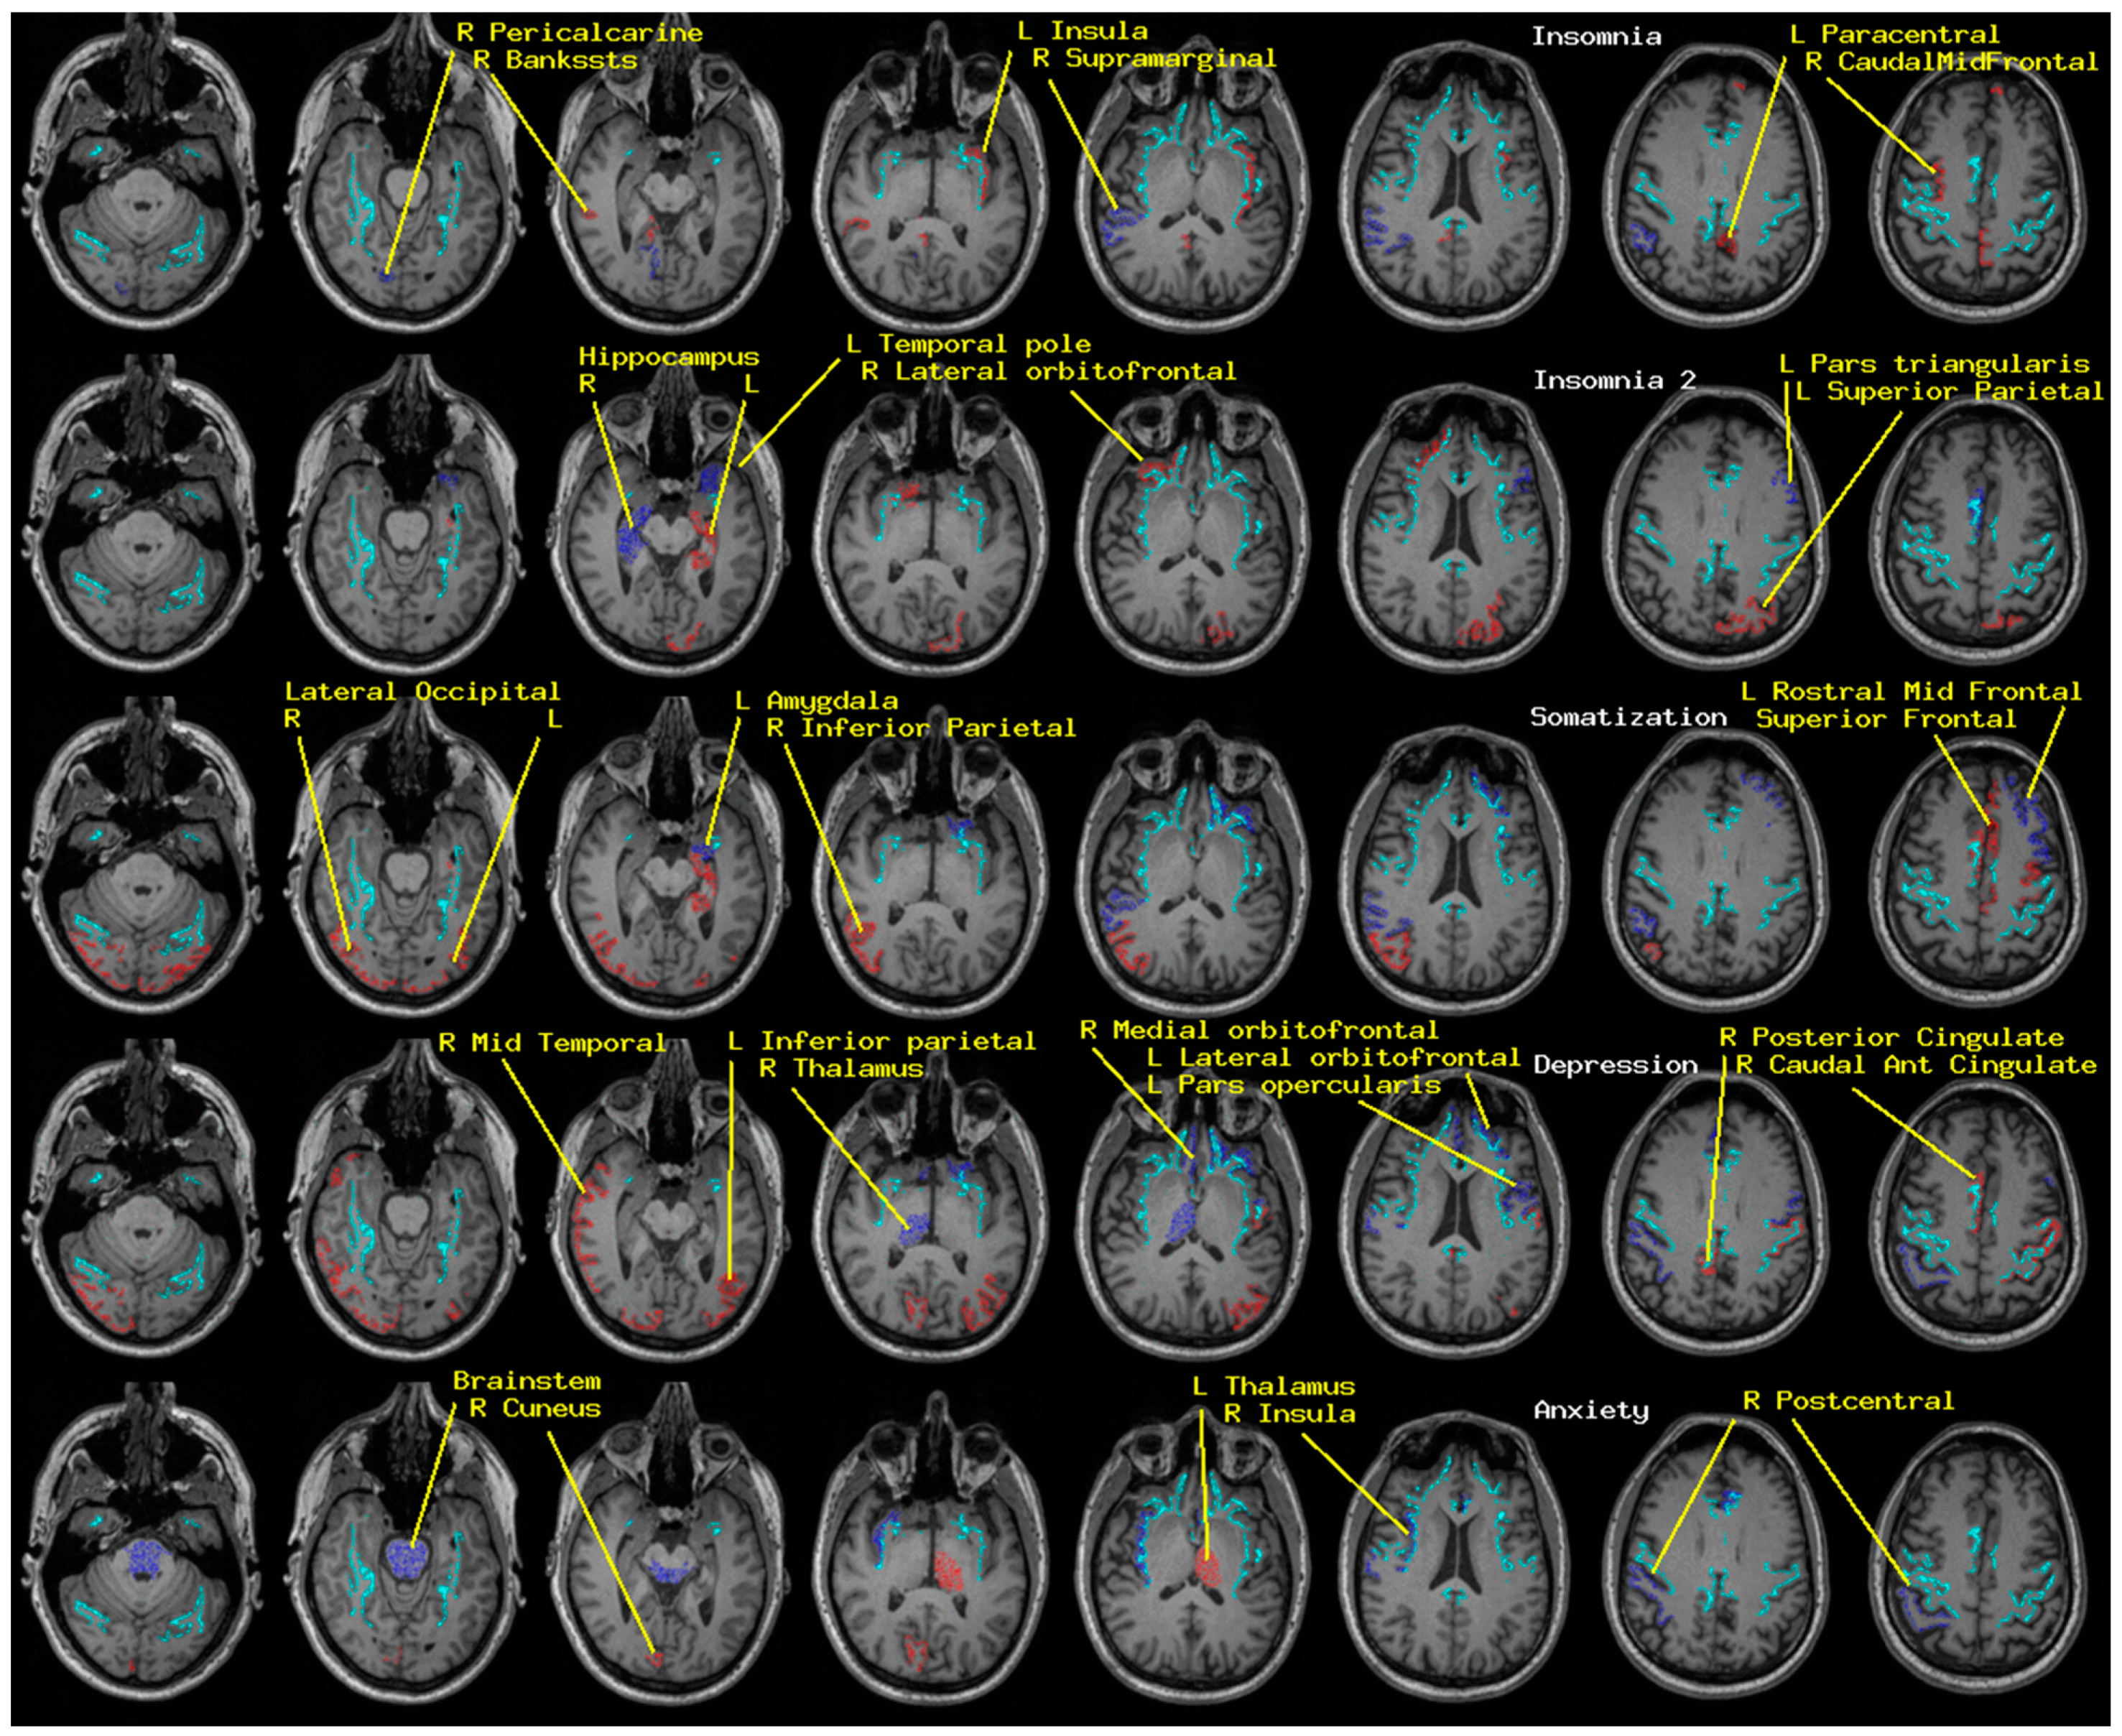

Regional measures of neuroelectric activity for 17 subcortical and 68 cortical regions were combined into classifiers using stepwise linear classification [16,17,18]. Classification accuracies with p-values are shown in Table 1 (Figure 1). The p-values were computed as follows. Considering line 1 of said table, 42 of 54 TEAM-TBI subjects who screened negative for insomnia were classified as negative and 12 as positive. The chance that this would happen by chance is equivalent to the odds of getting at least 42 heads when we flip a fair coin 54 times. For each symptom, both sides of the classification have significant p-values—i.e., the classifier does well in classifying both those who screen positive and those who screen negative. This provides confidence that the neuroelectric measures which comprise the classifier are related to the symptoms.

The regions whose measures were included are shown in Table 2 (Figure 1). For each symptom, a second classification function was constructed, for which the regions that were included in the first run were excluded. This second run produced significant classification accuracy for insomnia only, as indicated in the tables. This suggests (a) elevated confidence in the relationship between the regions whose neuroelectric measures were used for each classification and (b) that the regional measures included in the second classification function for insomnia are highly correlated with linear combinations of the first set. That is why they were not included in the first classification run.

Classification accuracy reached significance for all four symptoms for both clinically negative and positive groups. These results were weakest for anxiety. Classification accuracy was comparable for baseline and follow-up records; baseline vs. follow-up clinical rating changed for insomnia (n = 10), somatization (n = 9), depression (n = 10), and anxiety (n = 15), almost all for the better.